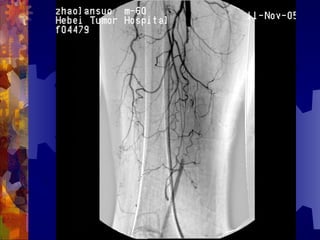

糖尿病足的检查

4. 足部 X- 线检查

5. 动脉造影(下肢)

男, 86 岁

双下肢多普勒血流图未探及血管

动脉造影血管闭塞